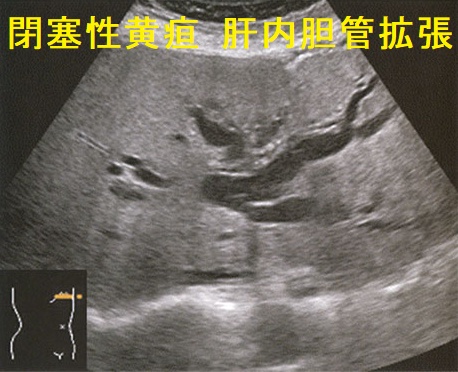

- 総胆管下部は膵臓に抱えられており、閉塞性黄疸に

Courvoisier徴候は、乳頭部癌、胆管癌、膵頭部癌などが原因で胆嚢管分岐部より下部の胆管が閉塞し、腫大した胆嚢を無痛性に触知する徴候です。

- 閉塞性黄疸を伴う